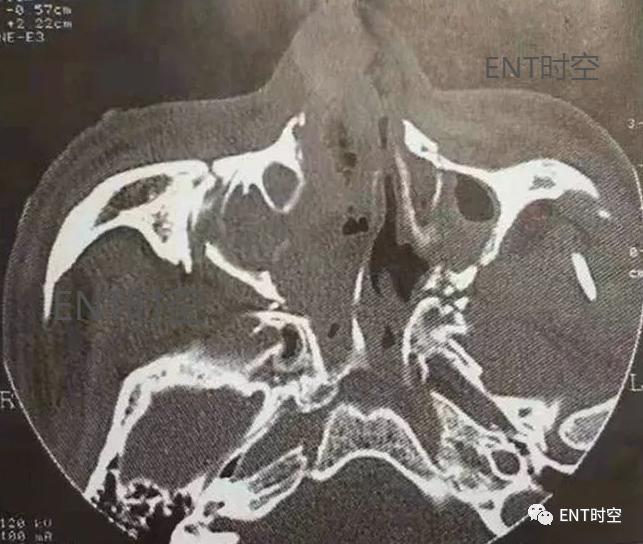

图2鼻-鼻窦多发骨折,轴位CT示上颌窦各壁及翼突多发骨折,上颌窦内积血。